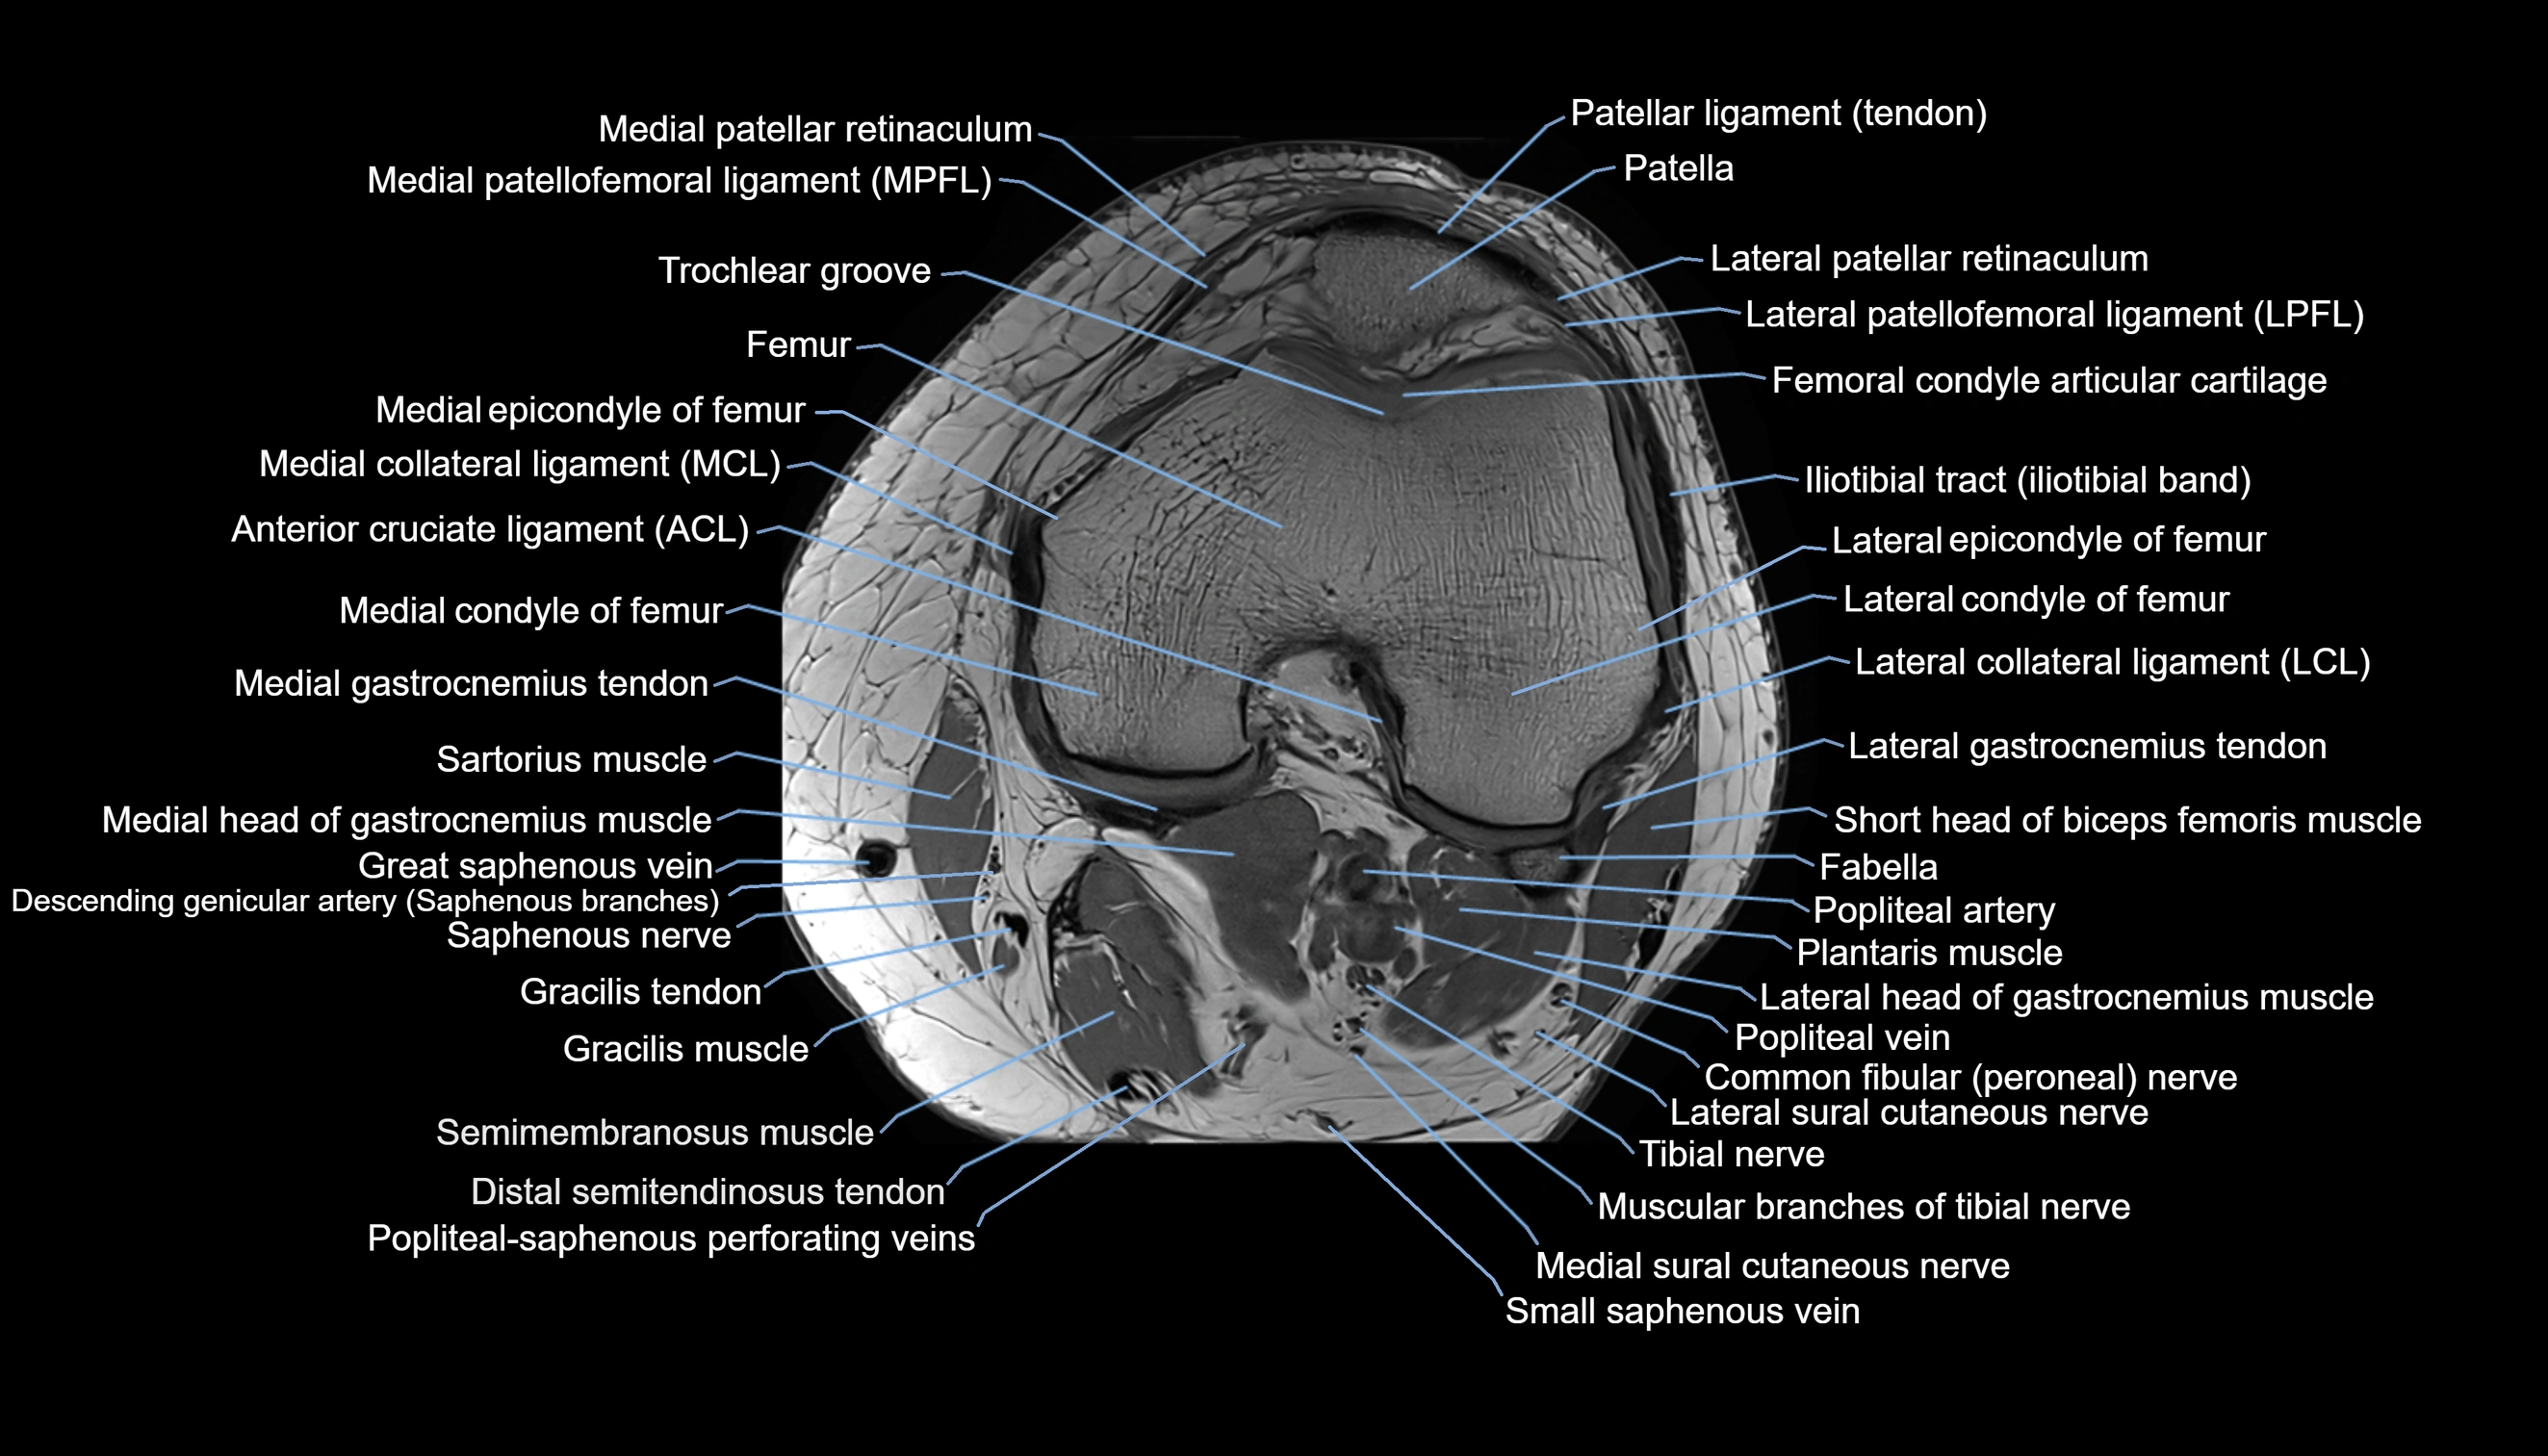

- Anterior cruciate ligament

- Femoral condyle articular cartilage

- Lateral collateral ligament

- Lateral condyle of femur

- Lateral epicondyle of femur

- Lateral gastrocnemius tendon

- Lateral head of gastrocnemius muscle

- Lateral patellar retinaculum

- Lateral patellofemoral ligament

- Medial collateral ligament

- Medial condyle of femur

- Medial epicondyle of femur

- Medial gastrocnemius tendon

- Medial head of gastrocnemius muscle

- Medial patellar retinaculum

- Medial patellofemoral ligament

- Medial sural cutaneous nerve

- Muscular branches of tibial nerve

- Patella

- Patellar tendon (patellar ligament)

- Plantaris muscle

- Popliteal artery

- Popliteal vein

- Popliteal–Saphenous perforating veins

- Saphenous nerve

- Sartorius muscle

- Semimembranosus muscle

- Small saphenous vein

- Trochlear groove

- great saphenous vein